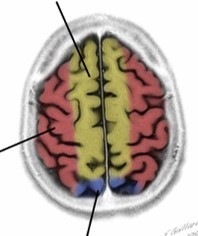

What do A and B represent?

A: Broca’s area

B: Wernicke’s area

Which lobes do each of the coloured areas represent?

Blue: frontal lobe

Yellow: parietal lobe

Green: temporal lobe

Red: occipital lobe